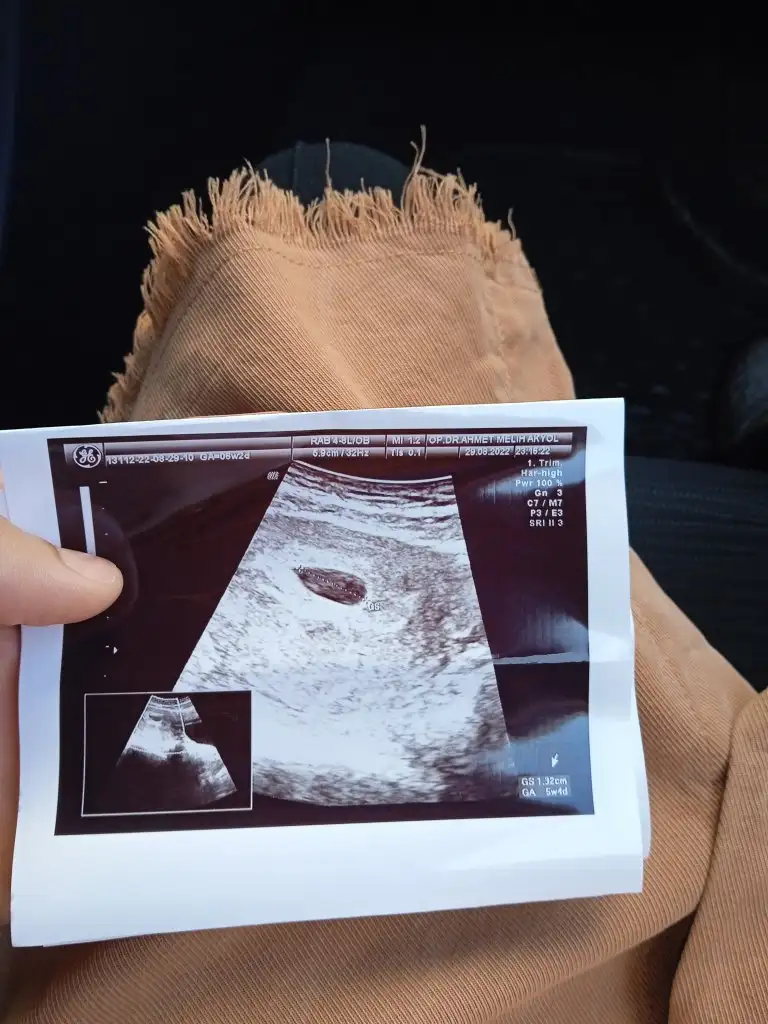

Banada bakarmısın canım hepside ultrason ile karından bakıldıSelam Kızlarbir çok kişi gruplardan beni bilir. Yine yetiştim imdatlara

5 ve 14. haftaya kadar olan ultrason fotolarınızı paylaşın. Vajinadan mı yoksa karından mı çekildiğini ve kaç haftalık olduğunu da mutlaka belirtin.